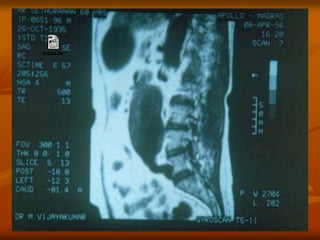

CT Imaging

 Precise test – provides good

images of aorta,aortic

lumen,branch vessels and

adjacent retroperitoneal

structures.

 Shows size and extent of

aneurysm and relation to renal

and iliac arteries.

 SPIRAL CT – 3 dimensional

image.